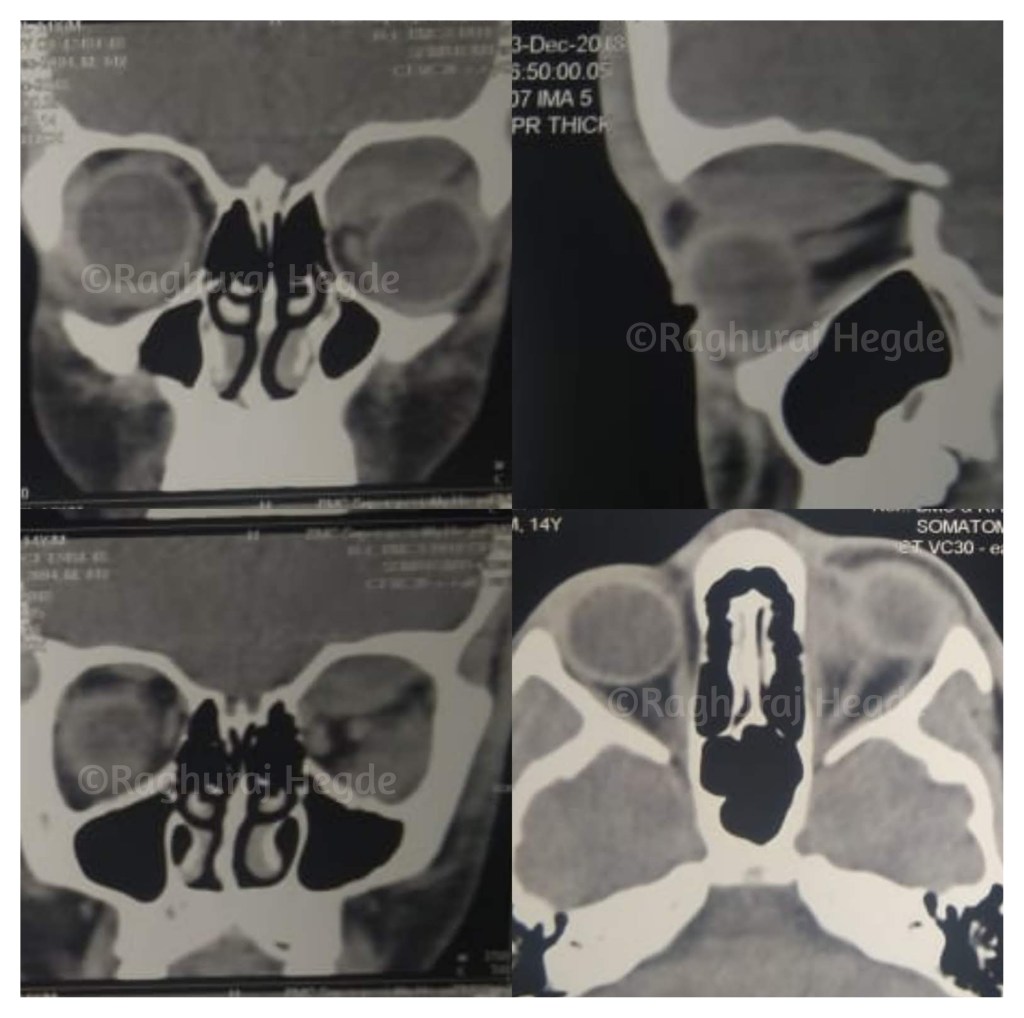

The CT showed a well defined mass in the supero-medial quadrant of the left orbit pushing the intraorbital contents outward and downwards. The mass was putting pressure on the optic nerve. All this explained the proptosis, diplopia and reducing vision.

The classical dome shaped mass limited by the orbital wall periosteum was either a sub-periosteal hematoma (SPH) or abscess. The diagnosis was veering more towards the former as there were no systemic signs of an infection and an isolated primary orbital abscess in an immuno-competent individual is very rare.

However the clincher in radiological diagnosis of a lesion is in the Hounsfield Units (HU). Hounsfield units (HU) represent a scale of radiation attenuation values of tissues. The number assigned is called the Hounsfield number. This particular number usually ranges from -1000 to +1000 HU or above. A higher number indicated a greater attenuation of X-rays thus meaning higher tissue density. Each tissue has a somewhat signature HU range. A dermoid cyst for example which is filled with fat has a HU value between zero and -100 while air can have a HU value around -1000. Calcification +100 and cortical bone +300 and above. A hematoma has a HU value between +50 to +80.

I called the Radiologist friend who was on his way home. I convinced him to return back to hospital to provide me the HU value for the collection causing the proptosis. Once he returned back to his console, he confirmed that the lesion has a HU value of +63 and sent me the confirmation with a photo.

If you are doctor and you’ve read thus far, you must be wondering why the initial CT scan had not picked up the SPH. The answer is in the slice thickness ordered. Most CT scan centres in India acquire CT scans at 5mm slice thickness to save time and radiographic films- thus cost per scan. The orbit’s length in an adult is around 40-50mm. In a child, if you order a CT scan with 5mm thick slice thickness there are going to be very few slices acquired of the orbit. So through averaging, it sometimes totally misses the orbital lesion or even a fracture. This has happened to my patients enough times for me to re-order scans to many of my paediatric patients whenever the clinical details don’t correlate with radiological imaging. In this case, my residents knew the protocol that I want the CT scans ordered- 1mm cuts, Axial, Coronal, Sagittal and 3D reconstruction, Zero Gantry!